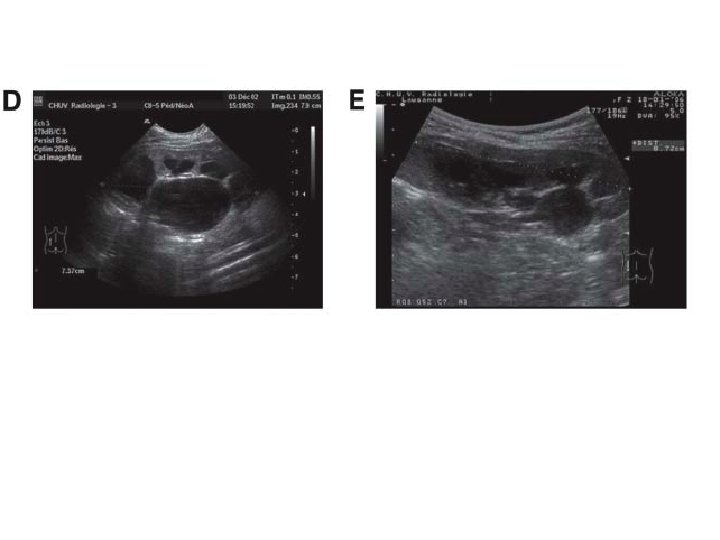

6/12 old boy, febrile UTI by age of 2/12, normal ultrasound and VCUG

9 year-old boy – febrile UTI

Left kidney 20 min after injection After miction 50 min after injection 4 year-old girl treated conservatively for left PUJ stenosis detected prenatally